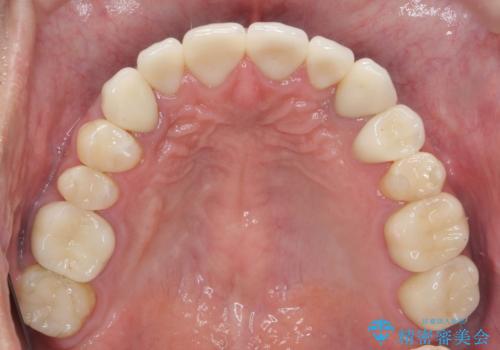

治療について

歯並びを整えたことで、歯ブラシのしやすさが向上し見た目も銀歯を全て除去したことで大きく改善して大変満足いただくことができました。